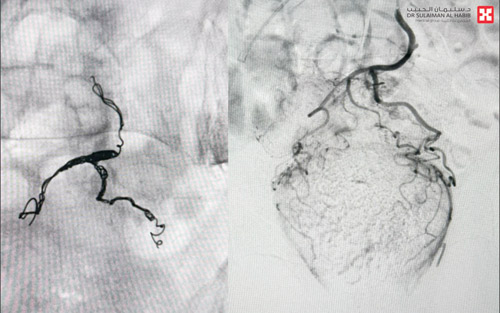

وأوضح د. الغراس أنه تم على الفور إخضاع المريضة لعدد من الفحوصات الطبية الدقيقة والتحاليل المخبرية قبل تحويلها مباشرة إلى قسم العناية المركزة، وقد كشفت نتائج الفحوصات الطبية عن وجود نزيف حاد في شرايين القولون والبواسير وتدنٍ شديد في نسب هيموجلبين الدم حيث وصلت إلى (6) علماً بأن النسبة الطبيعية هي (12)، وهو ما يفسر شعورها بالإرهاق والتعب الدائم. وأضاف أنه تم تكوين فريق طبي من استشاريي الأشعة التداخلية والقلب والعناية المركزة، وعقب دراسة كافة النتائج قرر الفريق إجراء عملية للمريضة باستخدام تقنيات الأشعة التداخلية لإيقاف النزيف بعد تقديم وحدات دم وريدية. وقد استغرقت العملية ساعة ونصف الساعة تحت التخدير الجزئي، وتم فيها استخدام أدوات طبية خاصة للسيطرة على النزيف وإيقافه بشكل تام. وبعد العملية نقلت المريضة إلى العناية المركزة لمدة 24 ساعة، وبعد ذلك تم تحويلها إلى جناح التنويم، وفي اليوم التالي خرجت من المستشفى وهي بصحة جيدة.